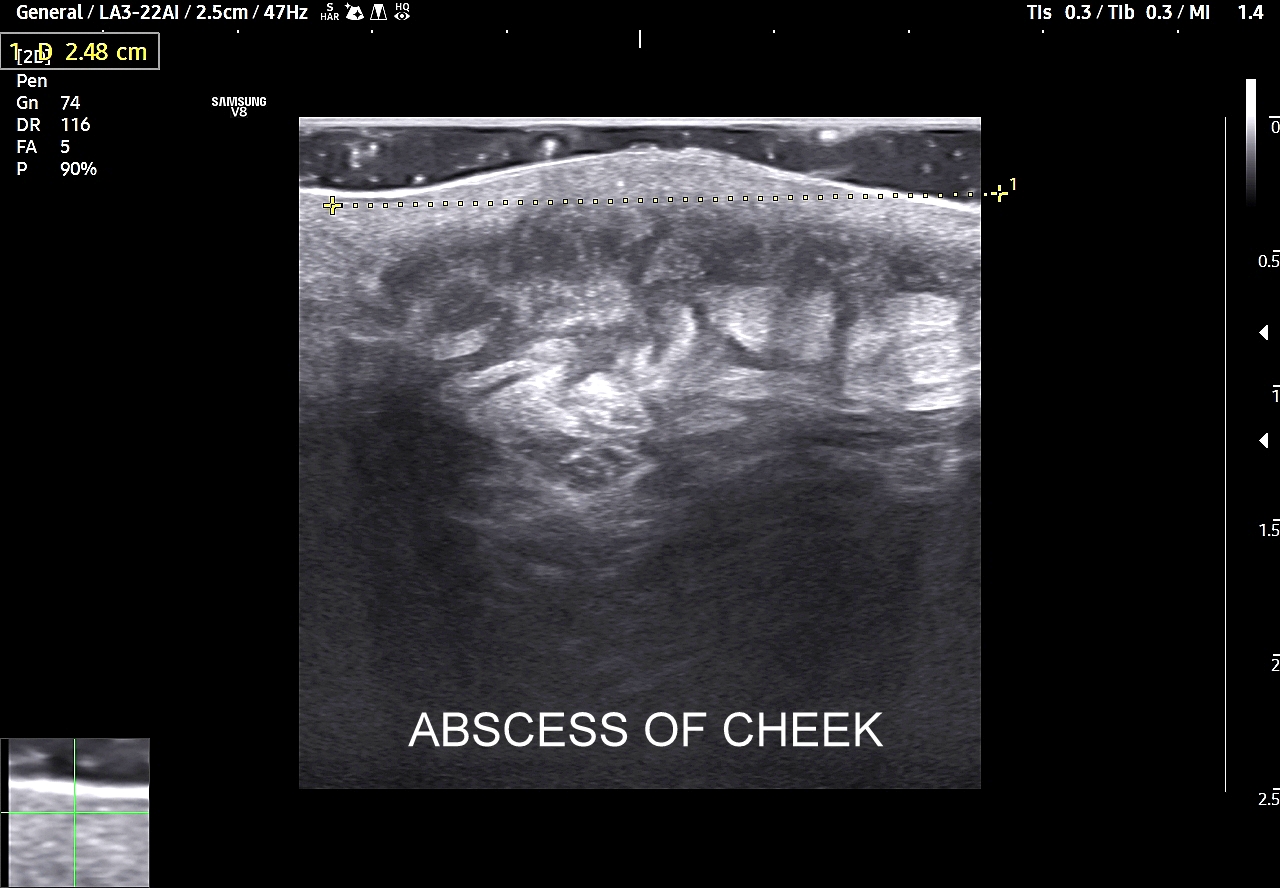

W kontekście powikłań żylnych związanych z trójkątem śmierci należy wspomnieć o zagrażających życiu powikłaniach wstępujących pod postacią zakrzepowego zapalenia zatoki jamistej i głębszych zatok wewnątrzczaszkowych skutkujących obrzękiem mózgu. Poprzez układ żylny oraz tętniczy rozprzestrzeniać mogą się również powikłania infekcyjne, których przykładem są zapalenie opon mózgowo-rdzeniowych i ropień mózgu. Źródłem powikłań infekcyjnych są zapalne stany skóry i tkanki podskórnej w obrębie twarzy oraz trójkąta śmierci, takie jak czyraki i ropnie. Z kolei powikłania zakaźne zstępujące to przede wszystkim infekcyjne zapalenie wsierdzia, zapalenie płuc, czy septyczna zatorowość płucna. Powikłania te związane mogą być również z modnym wśród młodzieży z piercing’iem nosa i warg.

Trójkąt śmierci na twarzy obejmuje również usta. Należy pamiętać, iż są one organami mocno unaczynionymi, co przedstawione jest na załączonych obrazach sonograficznych, a wszelkie infekcje ostre bądź przewlekłe, spontaniczne lub jatrogenne również mogą być przyczyną w/w infekcyjnych powikłań wstępujących oraz zstępujących.

Zapamiętaj! Badanie USG jest metodą pierwszego wyboru, a także gwarantuje wysoką czułość i specyficzności przy wykrywaniu oraz ocenie zmian chorobowych w obrębie twarzy. Z kolei trójkąt śmierci na twarzy to obszar o podwyższonym ryzyku poważnych powikłań w kontekście zabiegów z zakresu medycyny estetycznej oraz stanów ropnych w powłokach twarzy.